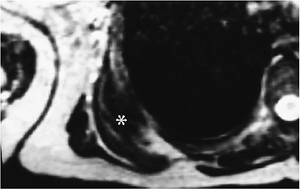

![]() |

|

FIGURE 10-52 Elastofibroma. Axial T2-weighted MR image showing a muscle density infrascapular lesion (asterisk) with linear areas of fat density.

P.731

FIGURE 10-53 Axial CT images demonstrate a subscapular mass (arrow) on the right with areas of fat infiltration.